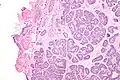

Micrograph of a Sertoli cell nodule. H&E stain.

A Sertoli cell nodule is a benign proliferation of Sertoli cells that arises in association with cryptorchidism (undescended testis).[1] They are not composed of a clonal cell population, i.e. neoplastic; thus, technically, they should not be called an adenoma.[2]

Sertoli cell nodules are unencapsulated nodules that consist of:[2][3][4]

- cells arranged in well-formed tubules (that vaguely resemble immature Sertoli cells), with

- bland hyperchromatic oval/round nuclei that are stratified, and

- may contain eosinophilic (hyaline) blob in lumen (centre).